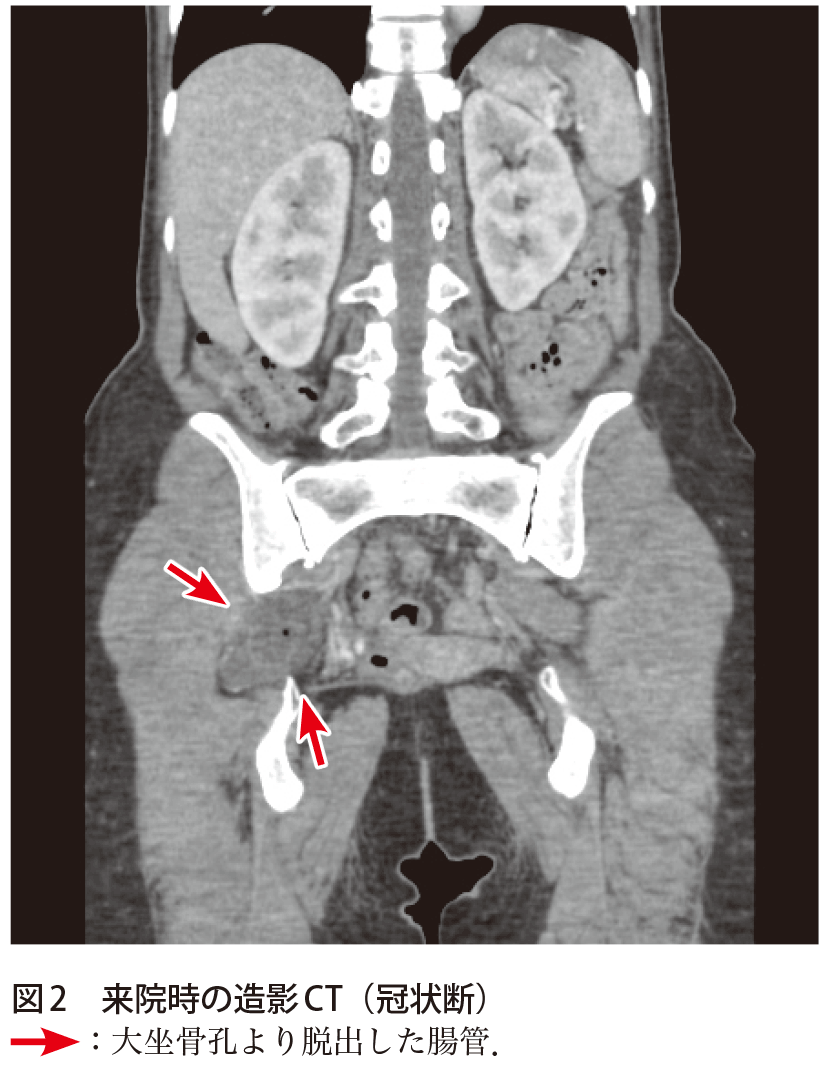

解答 解説 下腹部痛 右下肢痛を主訴に受診した40歳代女性 実践 画像診断q A 羊土社 レジデントノート 羊土社

右側腸骨静脈圧迫症候群に血管内治療を施行した1例 臨床雑誌外科 77巻8号 医書 Jp